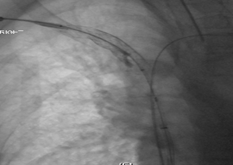

Final Image